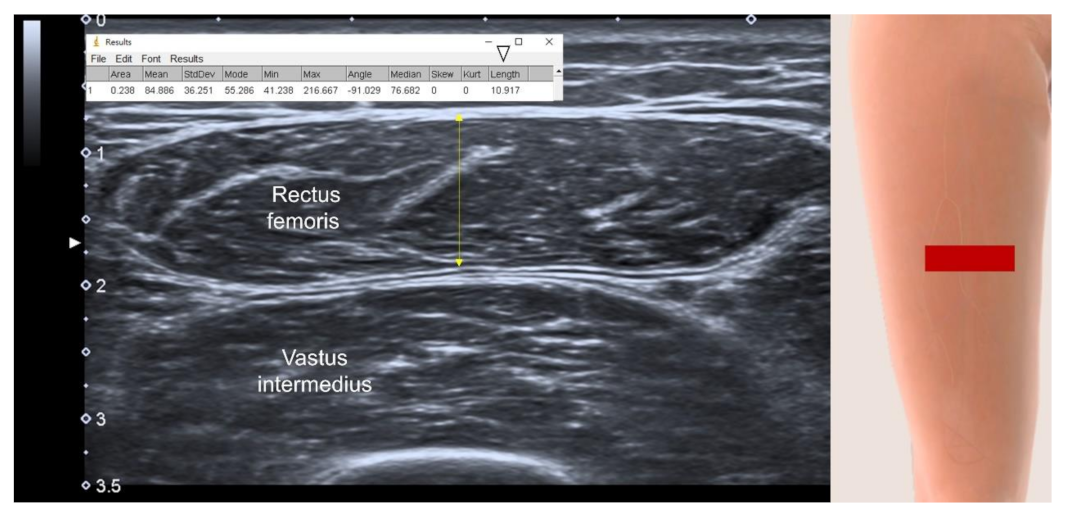

3.4.3. US parameters in B-Mode

3.4.4. Muscle Stiffness Measurement by Sonoelastography